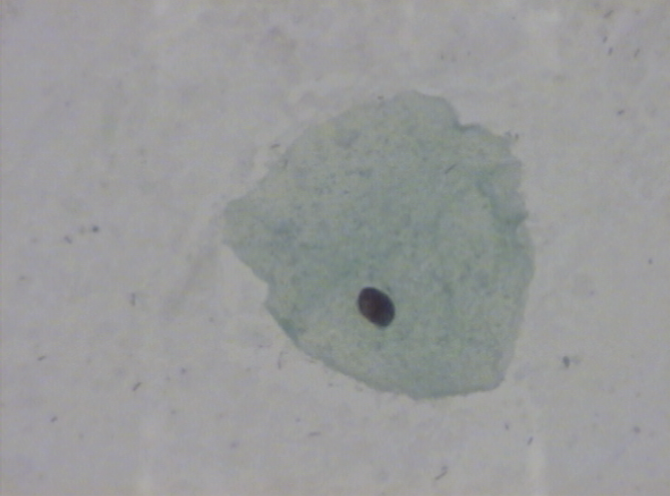

Here’s an example of benign cell findings.

Benign characteristics include large polygonal cells (superficial squamous cells) with abundant cytoplasm and small regular nuclei.